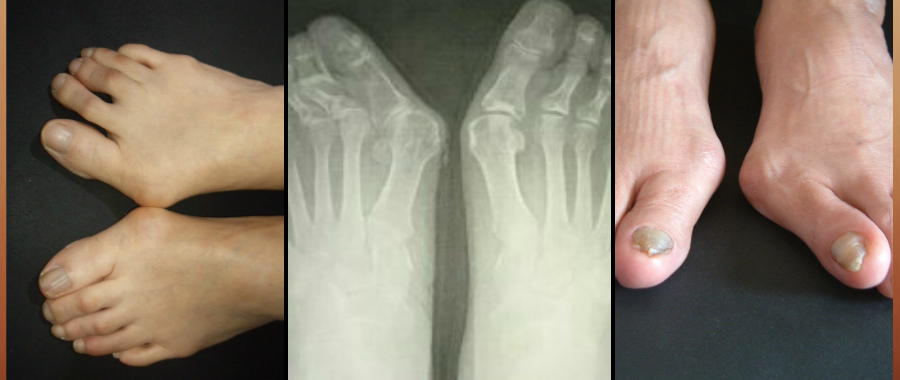

外反母趾、リウマチなどの変形、症状、痛みなどの悩みに

外反母趾、リウマチなどの変形、症状、

痛みなどの悩みに

外反母趾の害は

外反母趾だけに止まりません。